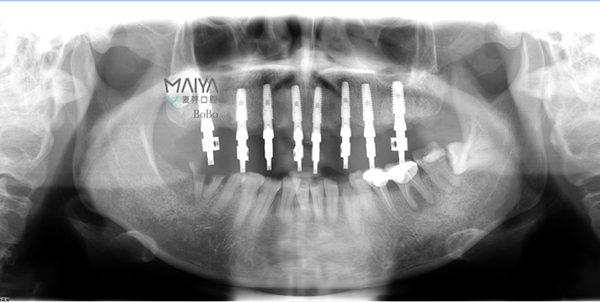

通过科学的德国卡瓦数字化口腔CT三维检测,麦芽口腔种植医师团队指出,由于长期对口腔疏于护理,郄女士的口内存有大量残根烂冠,咬颌空间不足,种植难度非常大,且上颌骨前突,为进一步达到美学效果,需要进行上颌前牙区牙槽骨修整术,整个治疗方案对医生的技术要求非常高。

根据郄女士的口腔内实际情况和她本人对牙齿美观/恢复咀嚼功能的要求,2015年底,麦芽口腔种植医师为其实施了半口无牙即刻种植、即刻修复技术。

术后口腔ct全景片